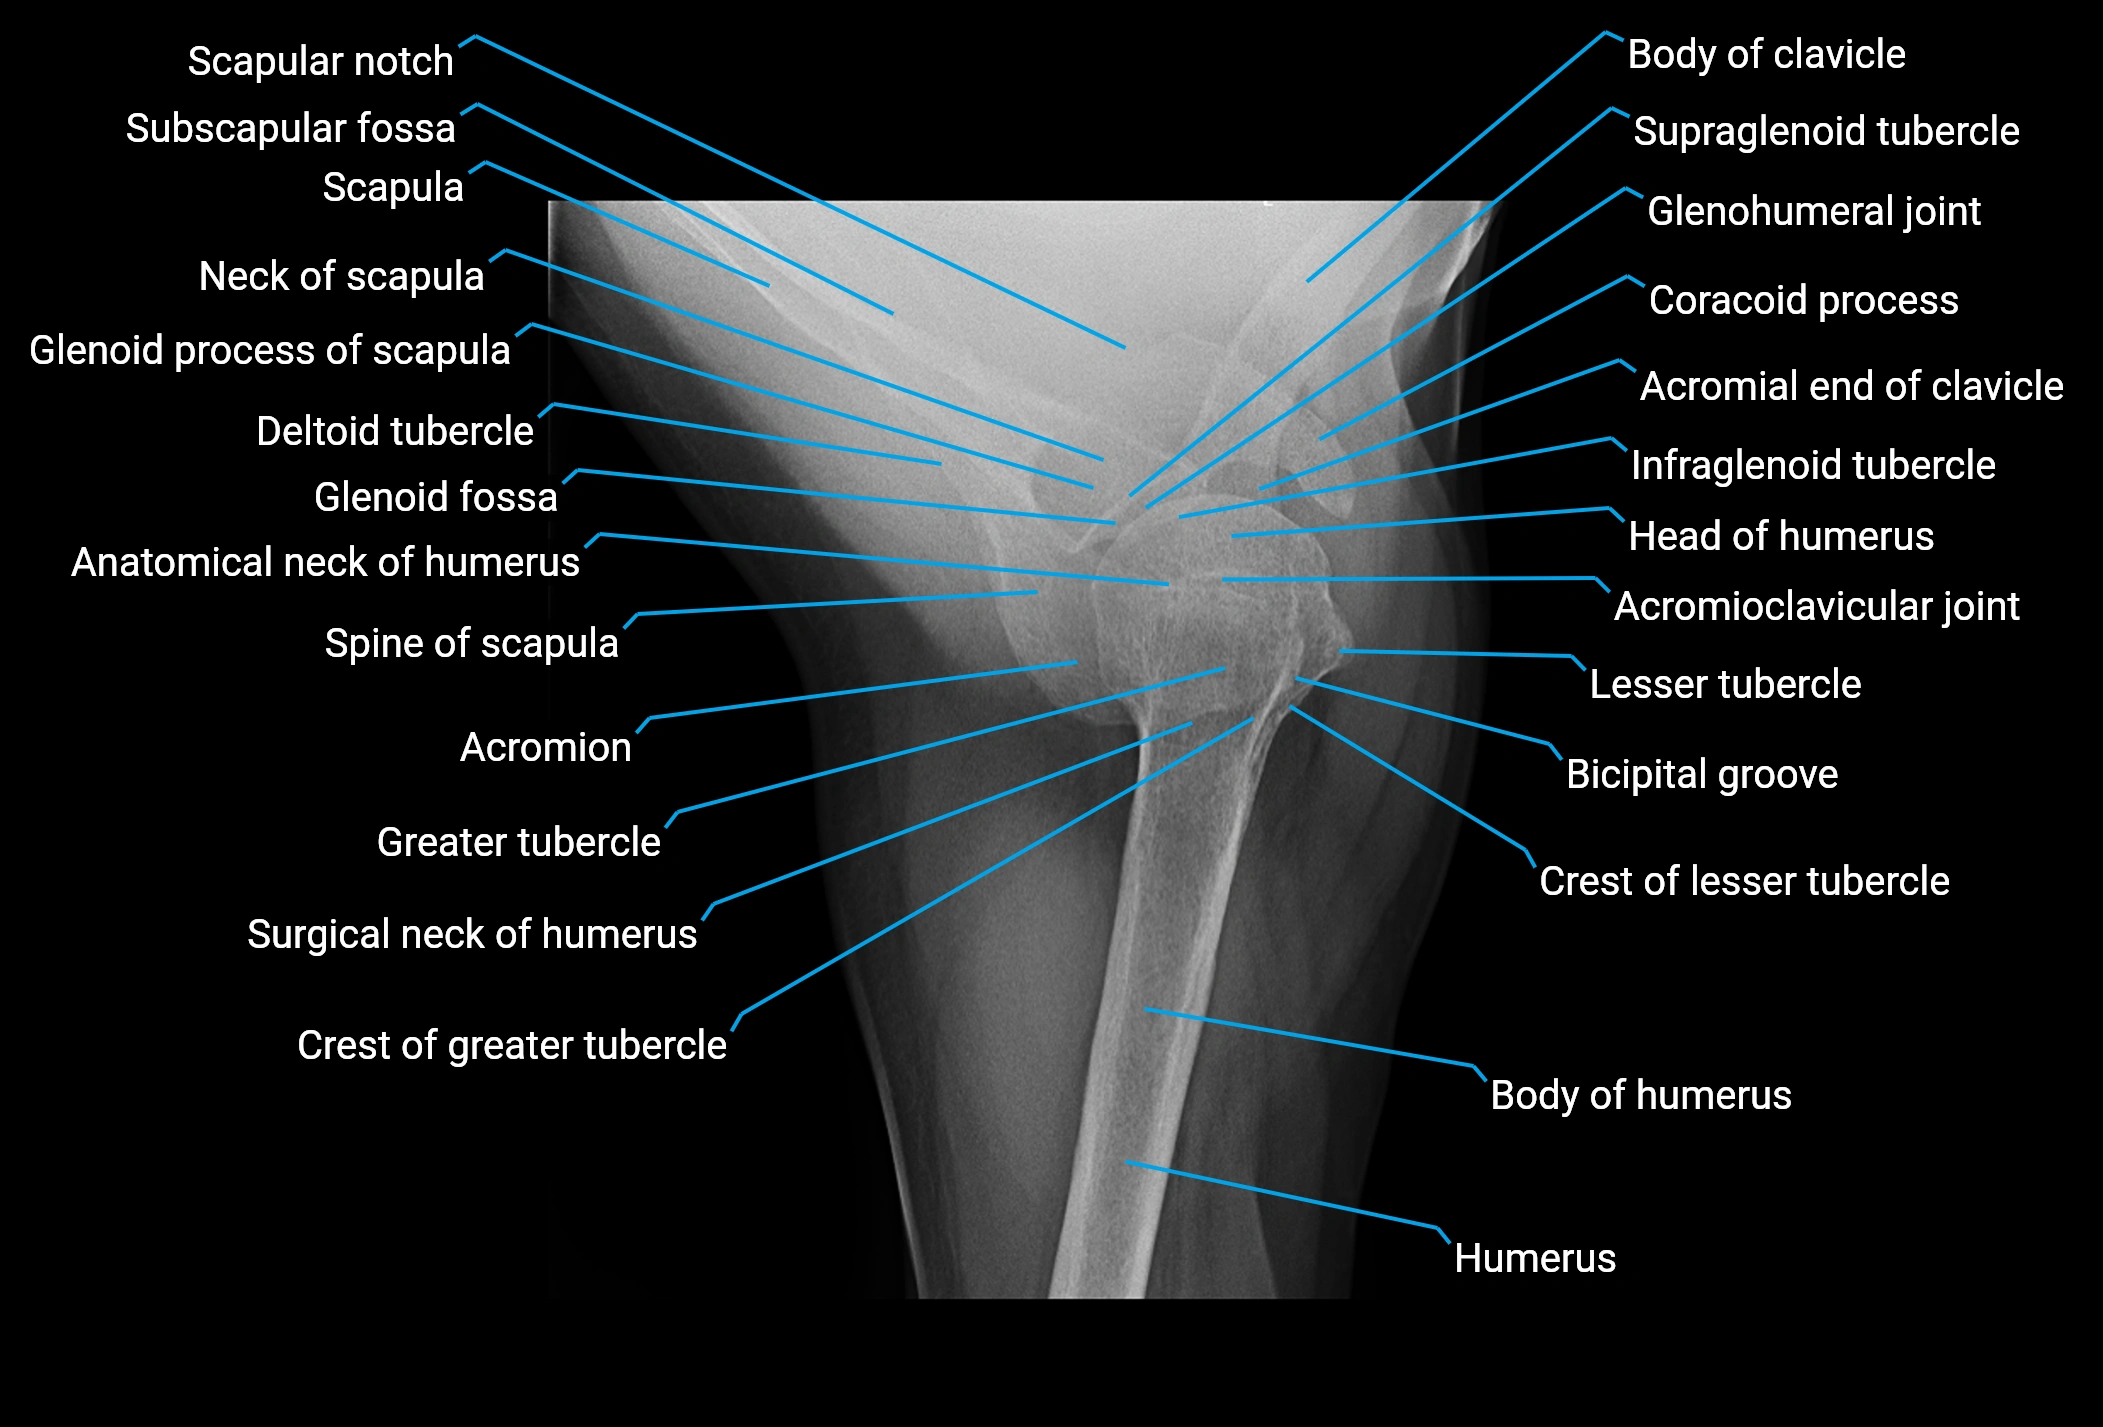

The acromial end of the clavicle is the flattened lateral extremity of the clavicle that articulates with the acromion of the scapula to form the acromioclavicular (AC) joint. Unlike the sternal end, the acromial end is broad and compressed. Its articular surface is oval, directed downward and medially, and covered with fibrocartilage.

The AC joint is stabilized by the acromioclavicular ligaments (superior and inferior) and reinforced by the coracoclavicular ligaments (conoid and trapezoid), which prevent vertical displacement. Small intra-articular fibrocartilaginous discs may be present.

This region is highly mobile, allowing scapular rotation, gliding, and elevation, which are essential for full shoulder motion. It is clinically significant as a frequent site of degeneration, separation injuries, fractures, and osteoarthritis.